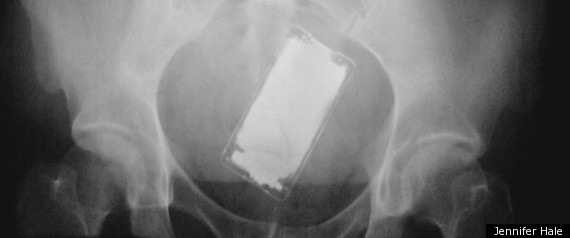

r-STUCK-UP-THERE-large570.jpg

Hey everyone, recently I sat down, felt a tremendous pain in my butt, and now I can't find my iPhone. Can anyone help me? Do you think "find my iPhone" will work?